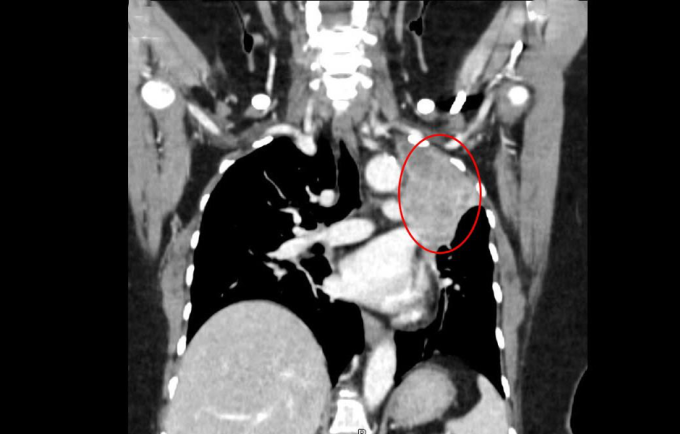

BS.CKII Nguyễn Trần Anh Thư, khoa Ung Bướu, Trung tâm Ung Bướu, cho biết các khối u ở não gây ra triệu chứng tương tự đột quỵ khiến người bệnh nhầm lẫn. Các khối u này có khả năng cao do ung thư di căn. Bác sĩ chỉ định chụp CT lồng ngực thùy trên phổi trái cho thấy khối tổn thương kích thước hơn 7 cm, bờ gồ ghề, gây xẹp phổi xung quanh.

Kết quả chụp CT thấy phổi trái bà Hoa có khối u hơn 7cm. Ảnh: Bệnh viện Đa khoa Tâm Anh